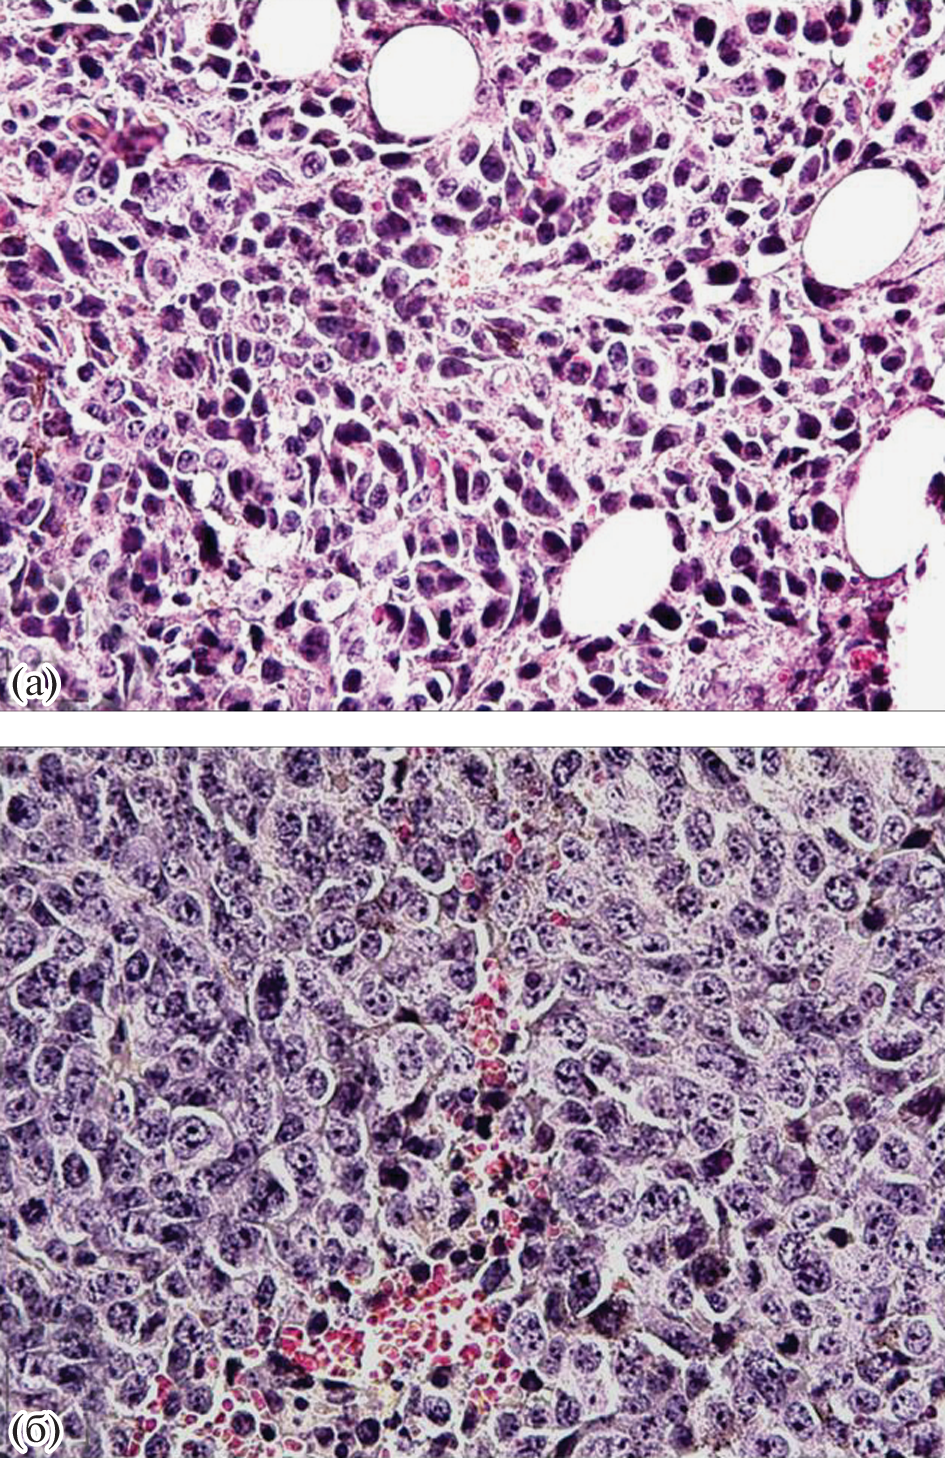

Целью исследования было изучение особенности роста и развития меланомы В16 у половозрелых самцов мышей С57Black/6 при моделировании посттравматического стрессового расстройства (ПТСР). Использованы поведенческие, иммуногистохимические, морфометрические методы, иммуноферментный анализ. Установлено характерное для ПТСР форсированное снижение уровня кортикостерона с последующей интенсификацией выработки клетками иммунной системы повышенных концентраций провоспалительных интерлейкинов и, одновременно, сокращение секреции противовоспалительных цитокинов. Получены приоритетные данные: нейрогуморальный дисбаланс, формирующийся при ПТСР, является сдерживающим фактором роста меланомы В16, по крайней мере, на начальных этапах развития онкологического процесса.